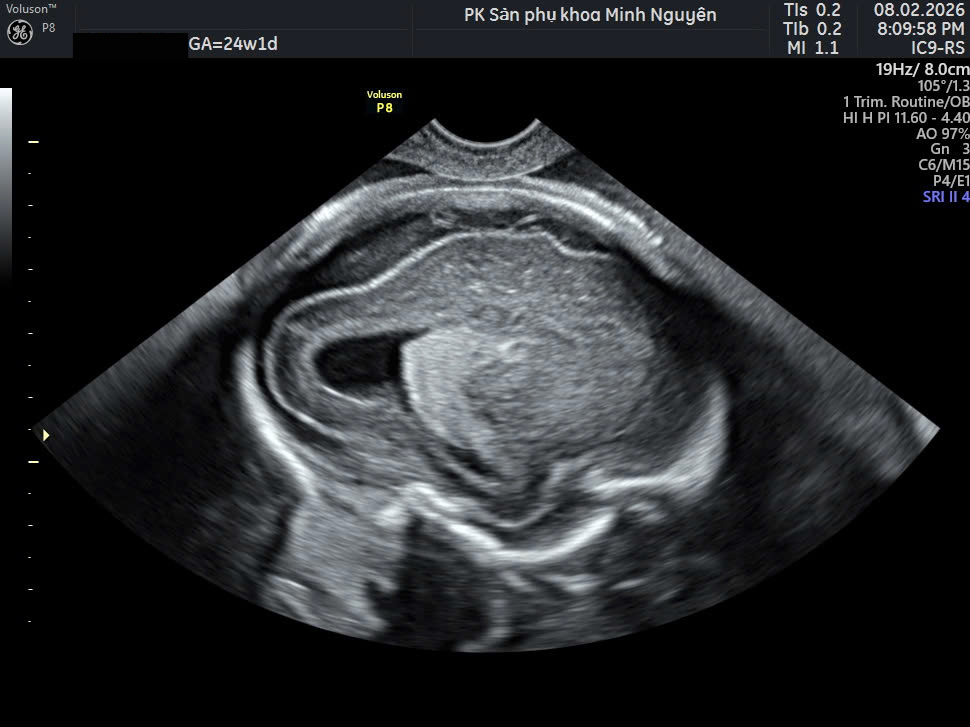

Giãn não thất thai nhi có giảm không là câu hỏi khiến nhiều mẹ bầu mất ngủ sau khi nhận kết quả siêu âm. Con số 10–12 mm nhìn qua tưởng nhỏ, nhưng lại đủ làm tim mẹ chùng xuống. Thực tế, không phải mọi trường hợp giãn não thất đều tiến triển nặng. Điều quan trọng là đo đúng, đánh giá đủ và theo dõi xu hướng theo thời gian.

Giãn não thất là tình trạng khoang chứa dịch trong não rộng hơn bình thường. Siêu âm đánh giá bằng kích thước não thất bên.

Chị H. đến phòng khám Dr Tú y học bào thai ở tuần 22+4. Phiếu siêu âm trước đó ghi: giãn não thất bên phải 11 mm.

Tại phòng khám, bước đầu tiên là đọc lại toàn bộ kết quả cũ. Sau đó đo lại đúng mặt phẳng, kiểm tra một bên hay hai bên, đánh giá nhu mô não và các cấu trúc thần kinh trung ương khác.

Kết quả đo lại là 10,8 mm, một bên, không có bất thường đi kèm. Kế hoạch theo dõi sau 2 tuần được thiết lập thay vì vội vàng kết luận.